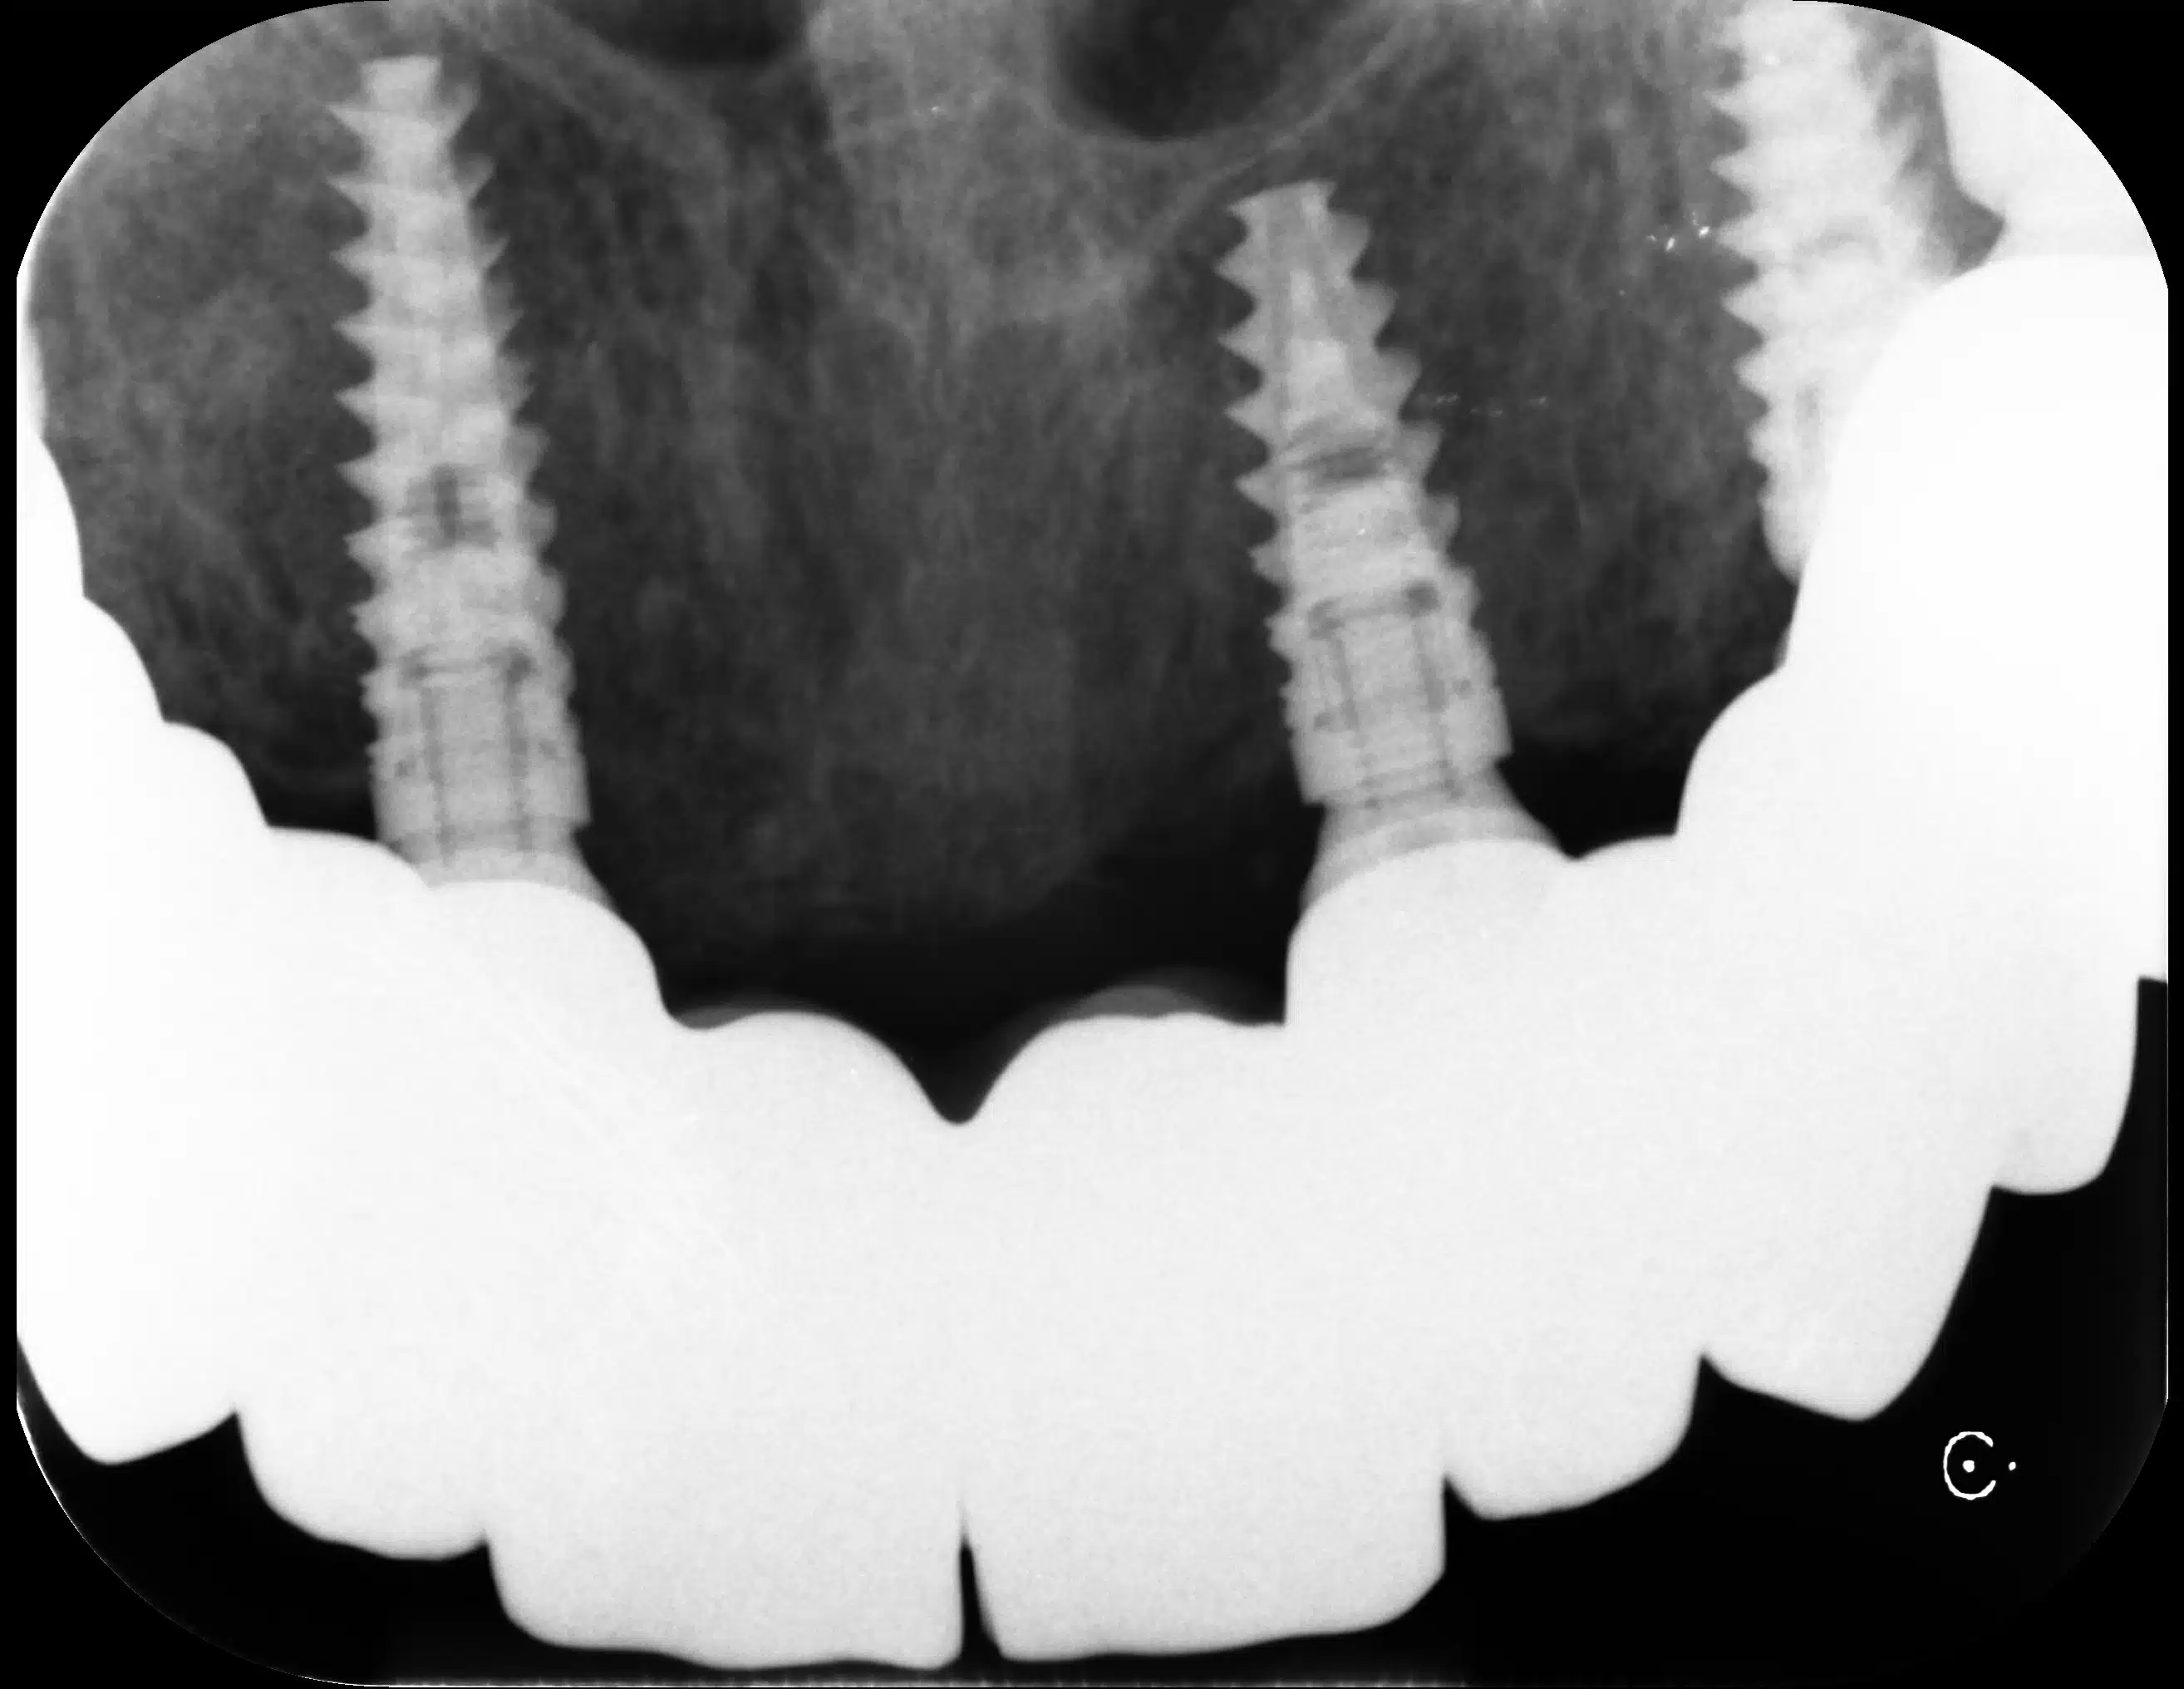

L’oro era, all’epoca, il principale materiale per la ricostruzione dei denti. Era utilizzato per otturazioni, corone e ponti. Dal punto di vista della durata è considerato tuttora il materiale migliore in assoluto.

Nei campi di concentramento più grandi c’era sempre anche lo studio del dentista. I dentisti delle SS lavoravano sotto il comando del medico generale del campo. L’oro dentale recuperato dai prigionieri morti, era anche utilizzato per curare gli ufficiali.

All’arrivo nei campi, veniva eseguito un esame medico di ogni prigioniero. Anche i dentisti delle SS avevano potere di vita o di morte sui nuovi prigionieri. Potevano decidere di ucciderli all’istante o inviarli al “lavoro”. In ogni caso, i denti d’oro sarebbero stati recuperati sempre, prima o dopo.

I corpi con denti d’oro venivano marcati con una croce blu o un filo corto su un dito. L’oro raccolto veniva inviato mensilmente al comando con una ricevuta che indicava il peso recuperato.

Ad Auschwitz, un team odontoiatrico apriva le bocche dei morti subito dopo le camere a gas ed estraeva tutti i denti d’oro con le pinze. Nel 1943 fu creata addirittura una fonderia d’oro nel Crematorio III. Secondo il sopravvissuto Filip Müller, venivano fusi da 5 a 10 kg al giorno, modellati in lingotti da 140 grammi.